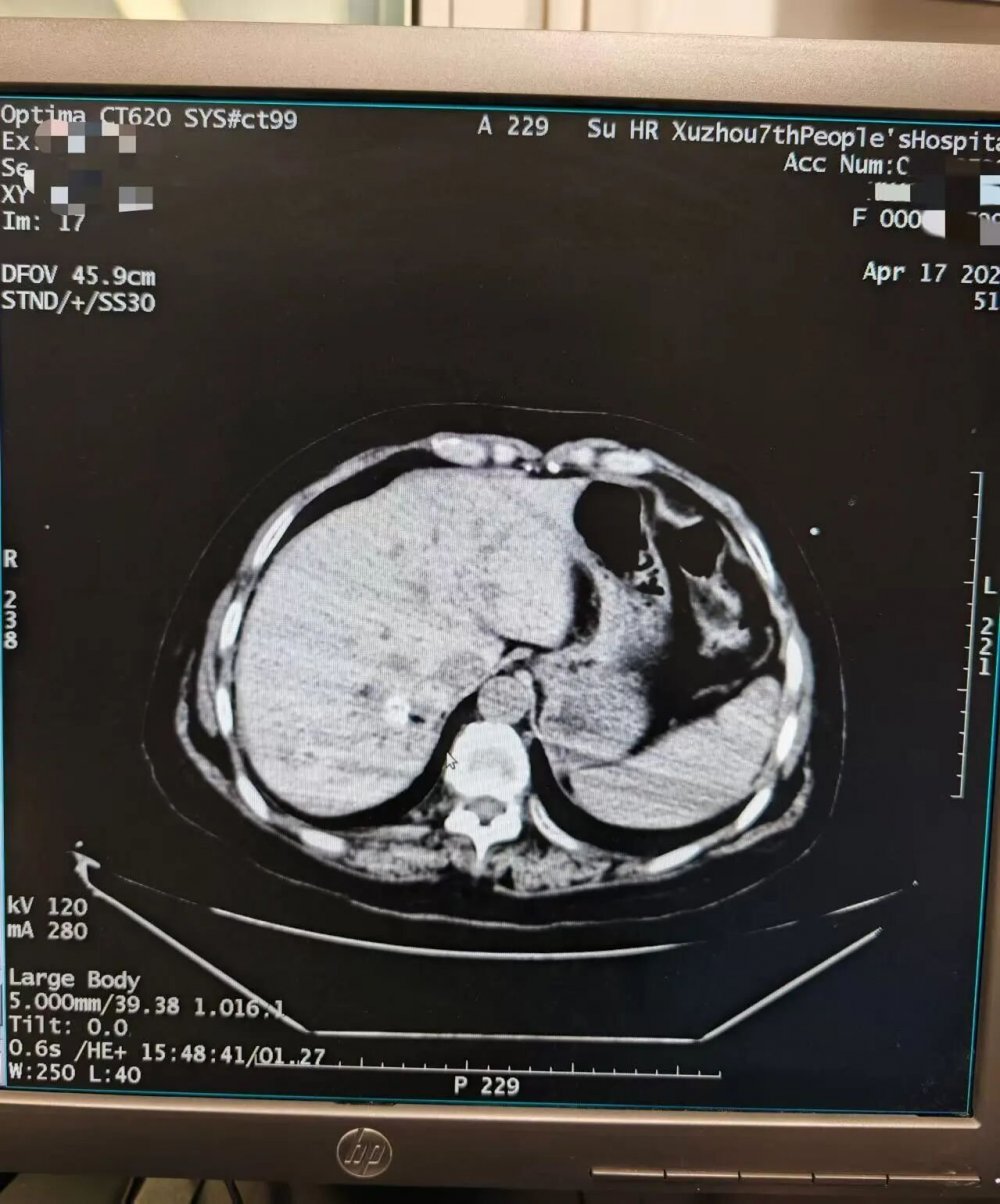

术前准备阶段,医护团队通过增强CT仔细研判病灶位置、大小及毗邻血管的关系,精准定位病灶核心区域,科学规划穿刺路径,反复推演操作细节,全力规避手术风险,为手术顺利开展筑牢坚实基础。

(图注:患者术前增强 CT 图像,清晰显示肝内病灶强化特征,为消融治疗提供精准定位依据)